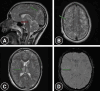

Fat embolism syndrome (FES) is a rare but serious complication most commonly associated with trauma, particularly long bone fractures. However, symptomatic FES remains a significant diagnostic and therapeutic challenge. We present the case of a 20-year-old man who, after sustaining multiple long bone fractures in a motorcycle accident and initially appearing stable, experienced a rapid and fatal progression of FES. This case underscores the unpredictable course of FES even in young, previously healthy individuals and highlights the critical need for early recognition and intervention. It also emphasizes the importance of identifying risk factors that may predict severe outcomes and mortality.